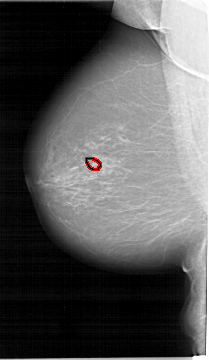

A_1649_1.RIGHT_CC

RIGHT_CC LINES 6166 PIXELS_PER_LINE 3571 BITS_PER_PIXEL 12 RESOLUTION 43.5 NON_OVERLAY

FILE: A_1649_1.LEFT_MLO.OVERLAY

TOTAL_ABNORMALITIES 1

ABNORMALITY 1

LESION_TYPE CALCIFICATION TYPE PLEOMORPHIC DISTRIBUTION CLUSTERED

ASSESSMENT 4

SUBTLETY 4

PATHOLOGY BENIGN

TOTAL_OUTLINES 1